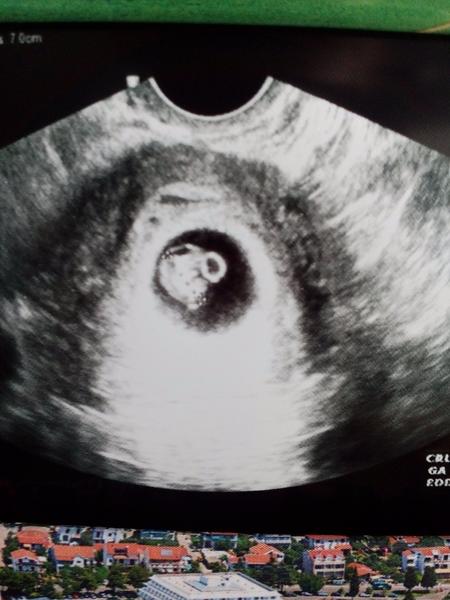

Baby tak tehu mam potvrdene,podla posl.ms som6+5 a dr.zatial nic konkretne neukazala len gulicku v maternici 🙂 . Kontrola o 2 tyzdne dufam ze uz bude srdiecko pocut. A je tam zatial len jedno 😉

@lenicka2609 baby tak u mna dnes takto, drobec má skoro 1cm 😃 teším sa 😉

Ahojte, tak už to mám potvrdené aj lekárom. Budeme mať bábo 🙂 🙂 som strašne strašne šťastná, že sa nám to podarilo 🙂 už mám aj prvú fotku, ale zatiaľ je to len taká malá 5milimetrová fazuľka 🙂 ale papám už za dvoch :D

@renusssska ja praveze celkom mavam fajn ale dva krat do roka to vystreli cca. Podla PM by som mala byt o tyzden popredu 6tt+6 dnes ale podla doktorky som o tyzden neskor...... co by aj podla sexu sedelo asi. Snad to tak je a vsetko je v poriadku 😍💓💞